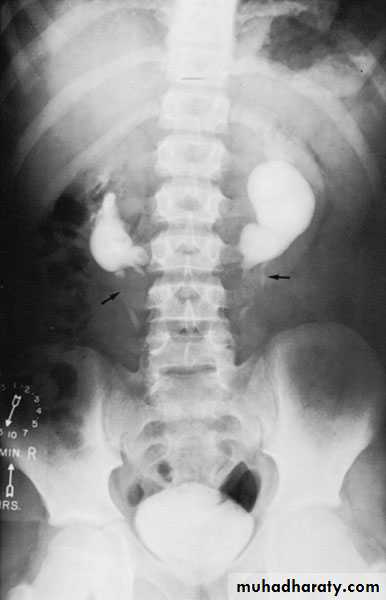

Congenital cystic kidney (polycystic kidney) (Adult cystic renal disease)

Autosomal dominant, transmitted by either parents, 50% of offspring affected.

Both kidneys replaced by large no. of cysts of variable size which make the kidney of large size.

The cysts contain clear fluid but sometimes blood.

The cysts progressively increase in size causing pressure atrophy of the renal parenchyma and pressing the ureter.

15% associated with cystic disease of liver, lung, pancreas or spleen.

Diagnosis: Family history of polycystic disease.

U/S, IVU, CT scan, MRI